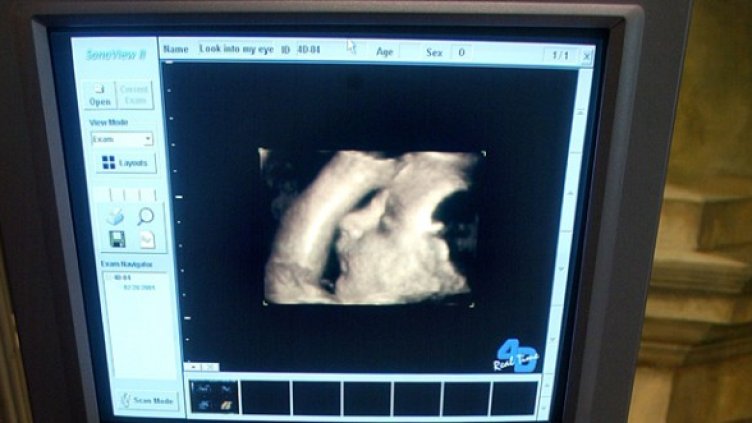

Нов закон за абортите в американския щат Тексас ще задължава жените, решили да прекъснат бременността си, да видят на ултразвук своето бебе 1-2 дни преди манипулацията.

Както съобщава American Independent, лекарят ще трябва да запознае пациентката си с резултатите от ултразвуковото изследване, а ако е възможно, да й пусне да чуе сърдечната дейност на плода.

Авторът на законодателната инициатива Сид Милър отбелязва, че по този начин бременната ще може напълно да осъзнае всички страни и възможни последици от аборта, който възнамерява да направи.

Според противниците на новия закон ехографският преглед само ще влоши емоционалното състояние на жената, която и без това е подложена на стрес в този момент.